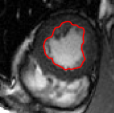

V-C LV and RV Segmentation: Quantitative Comparison to Commercial Software

We show experiments demonstrating the main use of our algorithm: in improving the prediction step of interactive segmentation methods. We show that less interaction is needed with our approach than a recent and widely used commercial cardiac segmentation software, Segment from Medviso [15, 44]. We perform quantitative assessment of the tracking performance of our method and compare it to Medviso. The evaluation was carried out on publicly available data sets, the MICCAI Left Ventricle Dataset [37] and the MICCAI Right Ventricle Dataset [25]. The validation dataset from [37] consists of 15 sets of cardiac cine-MRI images. Each set contains 6 to 20 2D slices from a 3D image, with each slice having 20 images of the cardiac phases. Similarly, the data set [25] contains 16 sets of cardiac cine-MRI images, each containing about 10 slices of 20 phases each. These data sets contain ground truth segmentations for left and right ventricles respectively (unfortunately ground truth for both the LV and RV is not available on a single dataset that we are aware of). Both methods start with the same initially correct segmentation, and subsequent frames are segmented via propagation. No manual interaction is used as we wish to show that our method would require less interaction. The regularity parameter in our method is found by choosing so that the results are closest to ground truth in a few training cases. The same parameter is then used for all other cases.

Figures 8 and 9 shows some sample tracking results of the proposed method and Medviso on full cardiac cycles of two different cases on both the LV dataset and the RV dataset. The ground truth (yellow) is superimposed when available. A summary of the results on the entire datasets is shown in Table I. The accuracy with respect to ground truth is measured using average perpendicular distance (APD) and dice metric (DM) for left ventricle, and Hausdorff distance (HD) and DM for the right ventricle. These metrics are chosen since they are the standard ones used on these datasets. Both qualitative and quantitative results show that our proposed method leads to more accurate segmentation of the ventricles and thus leads to less interaction than segmentation propagation schemes in than Medviso.